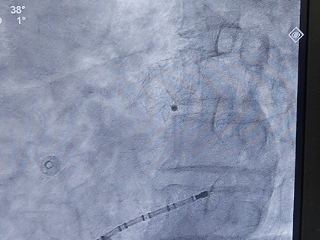

肝位输送LAFDQ-29封堵器

封堵器展开后造影

肝位

头位

牵拉试验后造影

牵拉稳定,且造影无残余分流。

测量压缩比

右肩位下测量压缩比为10.7%

封堵合适